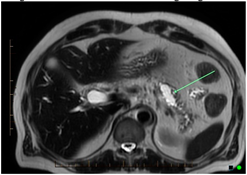

Computed tomography (CT)![]() | High sensitivity and specificity (76–92% and 67% respectively) Standardized available protocol- pancreatic protocol CT Multidetector CT Good spatial and temporal resolution Lower cost and greater availability | Radiation exposure with the risk of secondary cancer attributable to the CT procedure Performance depends on ability to administer intravenous Iodine contrast Allergies to CT contrast agents (common) Cannot detect iso-attenuating PDACs with indistinct borders and small pancreatic tumours |

Endoscopic ultrasound (EUS)![]() | High sensitivity and specificity (72% and 90% respectively) Excellent resolution for small lesions Mainly used as part of the work-up to obtain biopsy (FNA) for tissue diagnosis | Performance varies by disease T stage Invasive procedure, not practical for routine follow-up Not readily accessible imaging modality Highly dependent on technical skill of the operator Limitations for evaluating solid pancreatic lesions Procedural risks |

Magnetic resonance imaging (MRI)![]() | Highest sensitivity and specificity (93% and 89% respectively) Better soft tissue resolution No radiation exposure Better at determining metastasis Better accuracy for assessing local involvement of a pancreatic lesion | Can be difficult to obtain in patients with claustrophobia, metal devises, or allergies to gadolinium (very rare) |